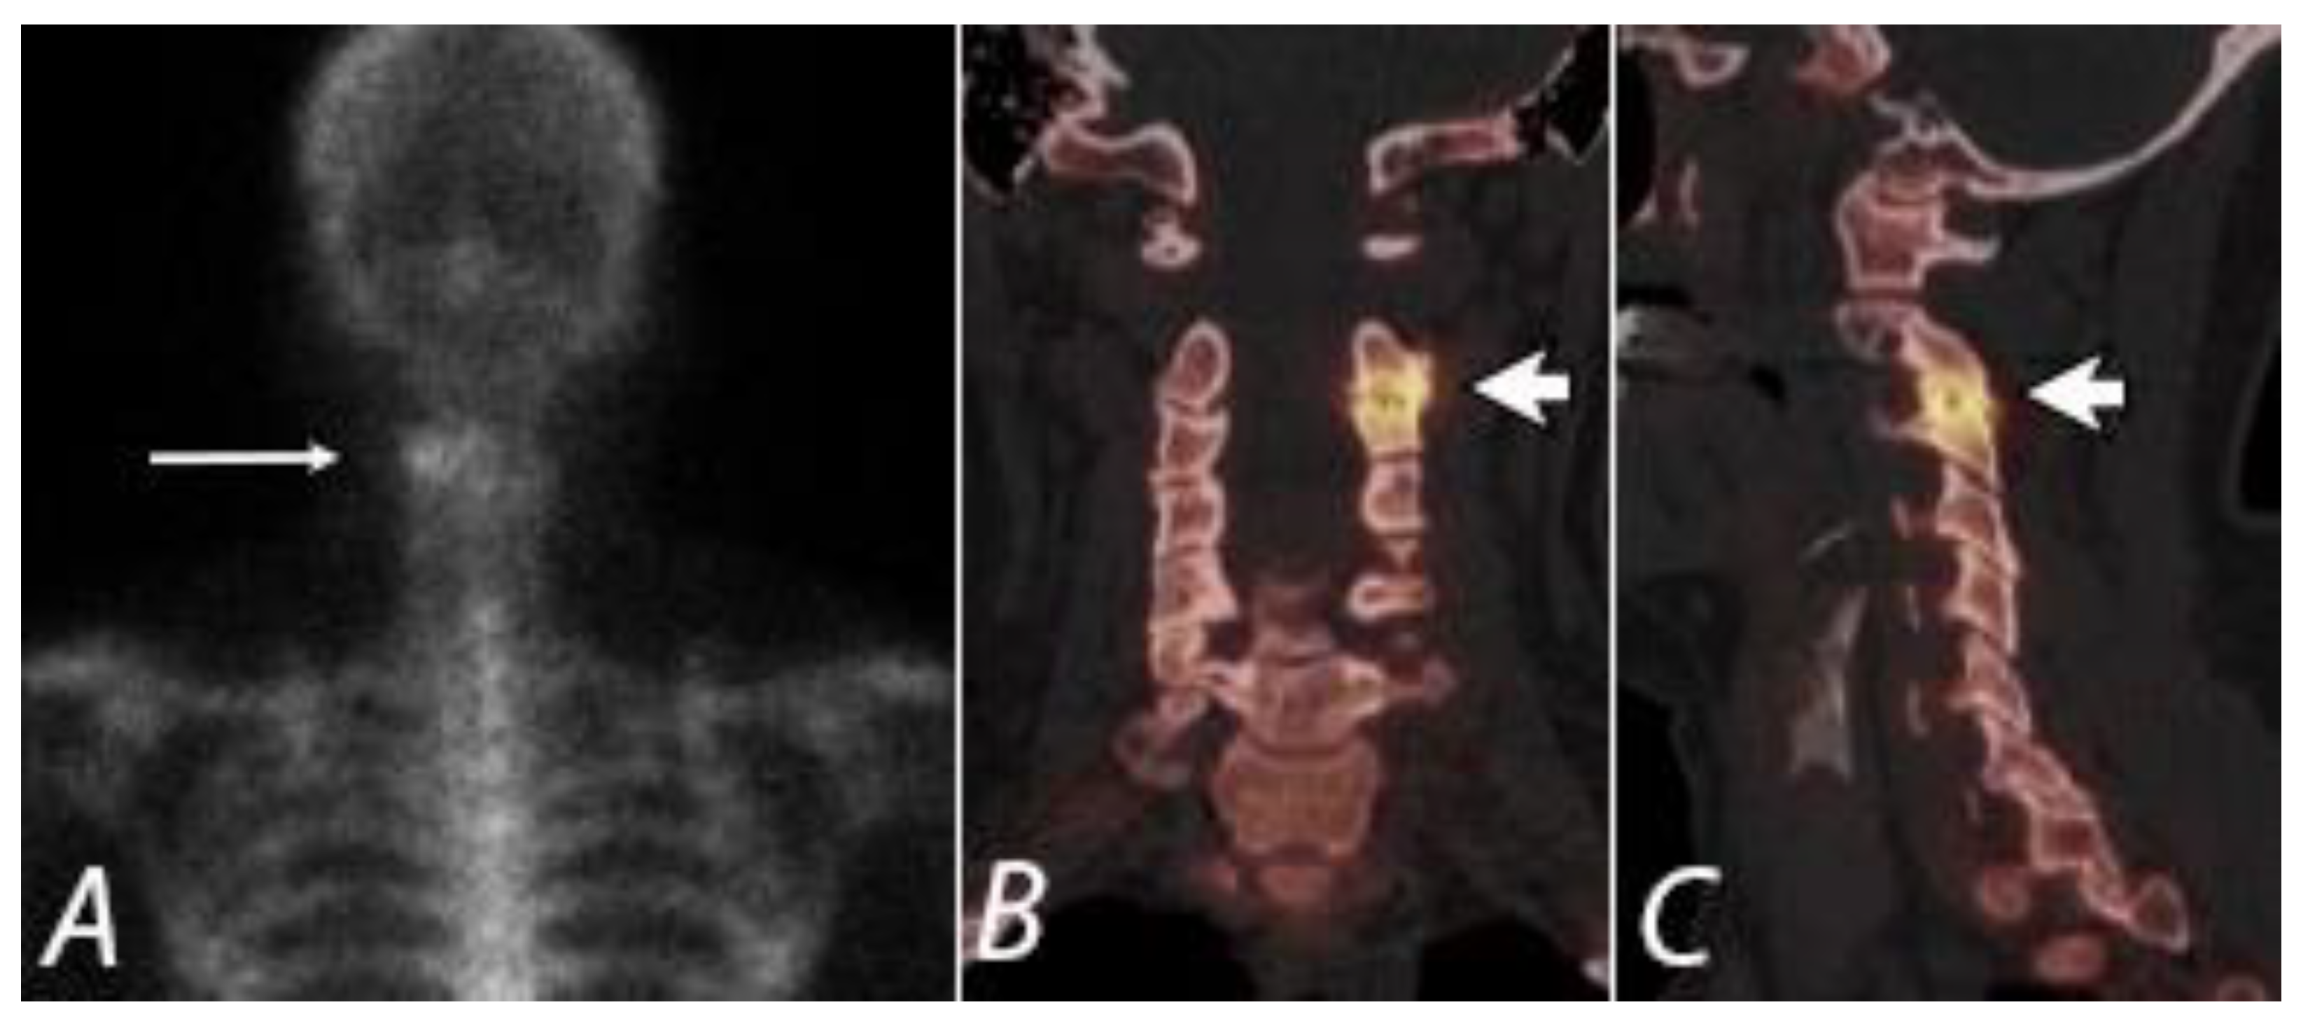

Chronic pain of spinal origin due to degenerative disease is a common encounter in clinical practice. Mechanical low back pain is a major health problem, which is associated with substantial economic and social costs [40] and accounts for up to 97% of low back pain diagnoses. It is mainly caused by degenerative disc disease, recurrent disc herniations, spondylolisthesis, degenerative scoliosis, or degenerative facet joint disease. Identification of the primary pain generator in these patients can be very difficult. Anatomic imaging modalities such as plain radiography, CT, or MRI can identify the sites of disc space degenerative and facet joint degenerative changes or other anatomic abnormalities but fail to accurately localize the exact sites of origin of pain. However, bone scintigraphy with SPECT or hybrid SPECT/CT imaging permits accurate localization of metabolically active sites of disease, thus aiding in appropriate management of these patients. 99mTc-MDP bone SPECT has been shown to be predictive of active facet joint disease [41,42]. In a study by Ryan et al., 34 patients with chronic back pain were examined to determine the nature and clinical relevance of lesions identified on plain radiography, CT, or bone scintigraphy with SPECT. Of 27 patients with lesions identified on SPECT, 24 (89%) had abnormal CT findings and 18 (67%) had abnormalities on radiography. SPECT aided in the identification of 54 lesions, of which only 20 (37%) were detected with planar imaging. 43 SPECT lesions were located at the site of an abnormality also seen at CT and 20 at the site of an abnormality also seen at radiography. They concluded that bone SPECT provides diagnostic information that is not available with radiography or planar imaging, and the majority of the lesions seen at SPECT correspond to identifiable disease at CT. Few studies have demonstrated the utility of SPECT in localizing active facet joint disease and identifying the sites for targeted facet joint injections [42,43,44]. SPECT and SPECT/CT can guide in therapeutic intervention by differentiating facet joint arthropathy from costovertebral joint osteoarthritis [43,44] (Figure 7).

Figure 7.

Posterior planar (A) (long white arrow), coronal (B), and sagittal (C) SPECT/CT images from a 99mTc bisphosphonate bone scan of a 43 year old women with left neck pain. Marked radiopharmaceutical uptake corresponds to a severely degenerative left C2/3 facet joint (short white arrows), identifying a potentially targetable pain generator.